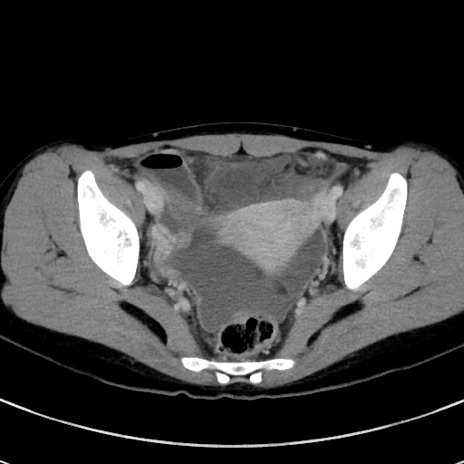

症例17(横断像)

冠状断像

【症例】20歳代女性

【主訴】嘔吐、下腹部痛

【現病歴】昨日夕食後に嘔吐し下腹部痛が出現。本日になっても嘔吐持続し改善しないため来院。

【身体所見】意識清明、BT 37.2℃、BP 108/67mmHg、腹部:平坦、やや硬、下腹部正中から右にかけて圧痛あり、反跳痛軽度あり、tapping pain(+)。

【データ】WBC 13600、CRP 14.94